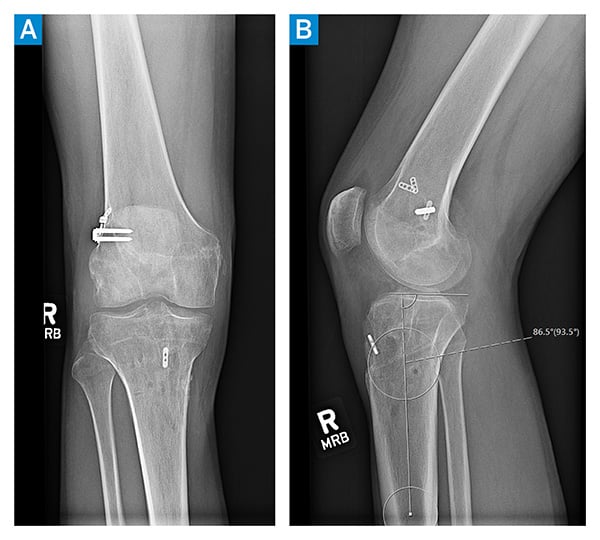

The patient underwent anterior closing wedge high tibial osteotomy with medial meniscus repair, hardware removal, and bone grafting of the prior ACL tunnels. Six months later, he underwent hardware removal, revision ACL reconstruction, and lateral extra-articular iliotibial band tenodesis. The latter was indicated given the multiple failures of prior ACL reconstructions, along with high-grade laxity (grade-3B Lachman, grade-3 pivot shift). His final physical examination demonstrated a 1A Lachman, no pivot shift, and stable collateral ligaments. There was full extension without hyperextension, and he flexed to 135°. The tibial subluxation had resolved, and the posterior slope was reduced to 4° (Figures 3 and 4). He returned to an active lifestyle but was counselled against returning to high-pivoting sports, given his extensive history of instability.

Figure 4: Postoperative right knee anteroposterior (A) and lateral (B) X-rays show reduced slope to 4° and no tibial subluxation.